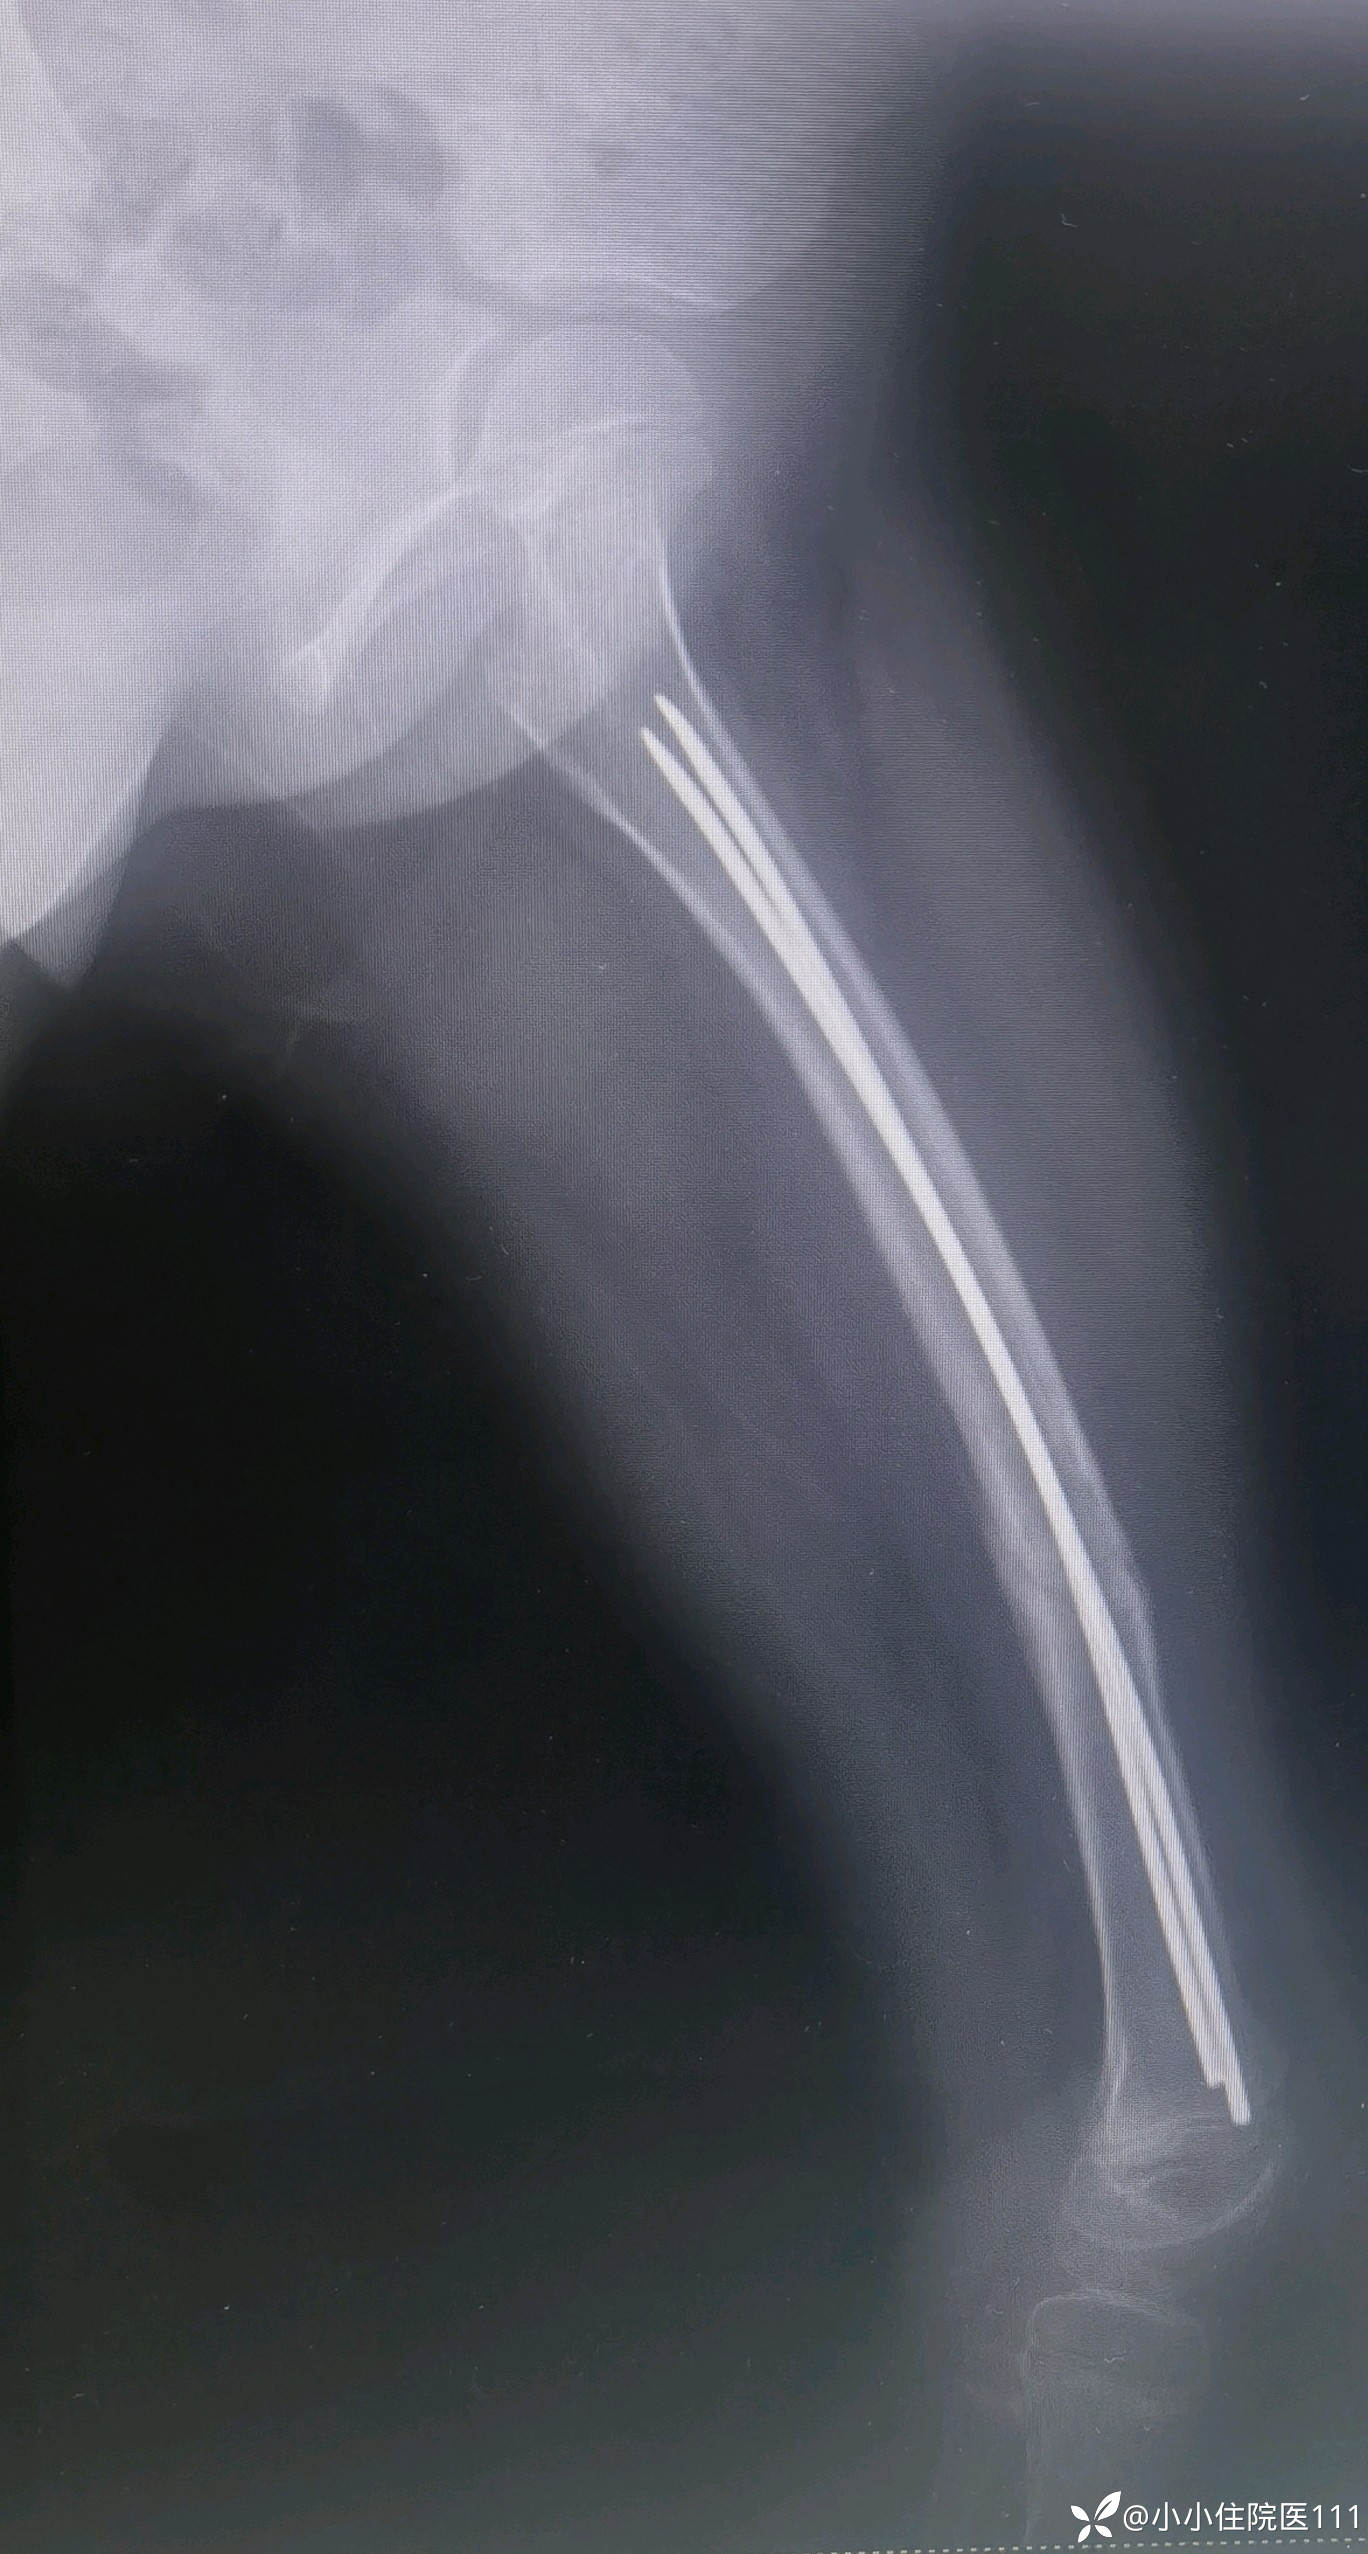

(2023-06-09)复查左股骨正侧位片

(2023-07-09)复查左股骨正侧位片

(2023-08-28)复查左股骨正侧位片